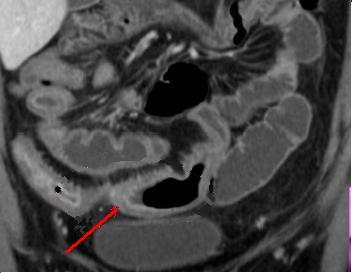

| Epaissisement parietale avec

oedeme de la sous muqueuse ( fleche rouge ) . Image

de fissuration legere peut se voyait un peut dans ce

cas . Maladie de Crohn de ileon en coupe TDM

coronale |